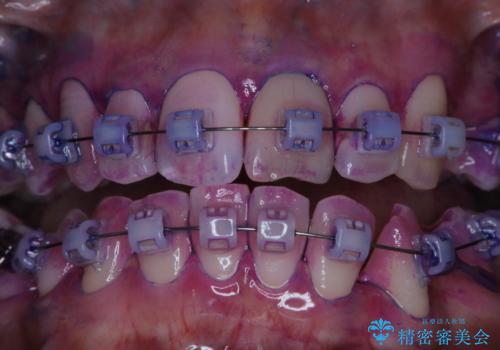

- ワイヤー矯正中に、口臭や汚れが気になり綺麗にクリーニングしたいとのことでした。染め出しをしての歯磨き指導とPMTC60分コースを行いました。

ワイヤー矯正中はブラッシングが難しくなるため、磨き残しが多くなることがあります。

ご自身でのブラッシングケアでは、歯周ポケットの中に歯ブラシの毛先が届くのはわずか2ミリ程です。軽度の歯周炎の場合でも歯周ポケットは3ミリほどあります。歯茎の中に長く汚れが溜まると、歯石や細菌などがつき、口臭の原因にもなります。

適切な道具を使って、適切なブラッシング方法を習得することで、磨き残しを減らすことができます。

また、矯正で歯の移動があると今までなかったところに隙間が出てきたり、ガタつきが解消されてきたりすることで、お口の中の環境が変わります。

矯正治療中も清潔な口腔内を保つことは、とても大切です。そのため、定期的に専門的な機械・材料を使用したProfessinnalcleaning(pmtc)を行うことがおススメです。